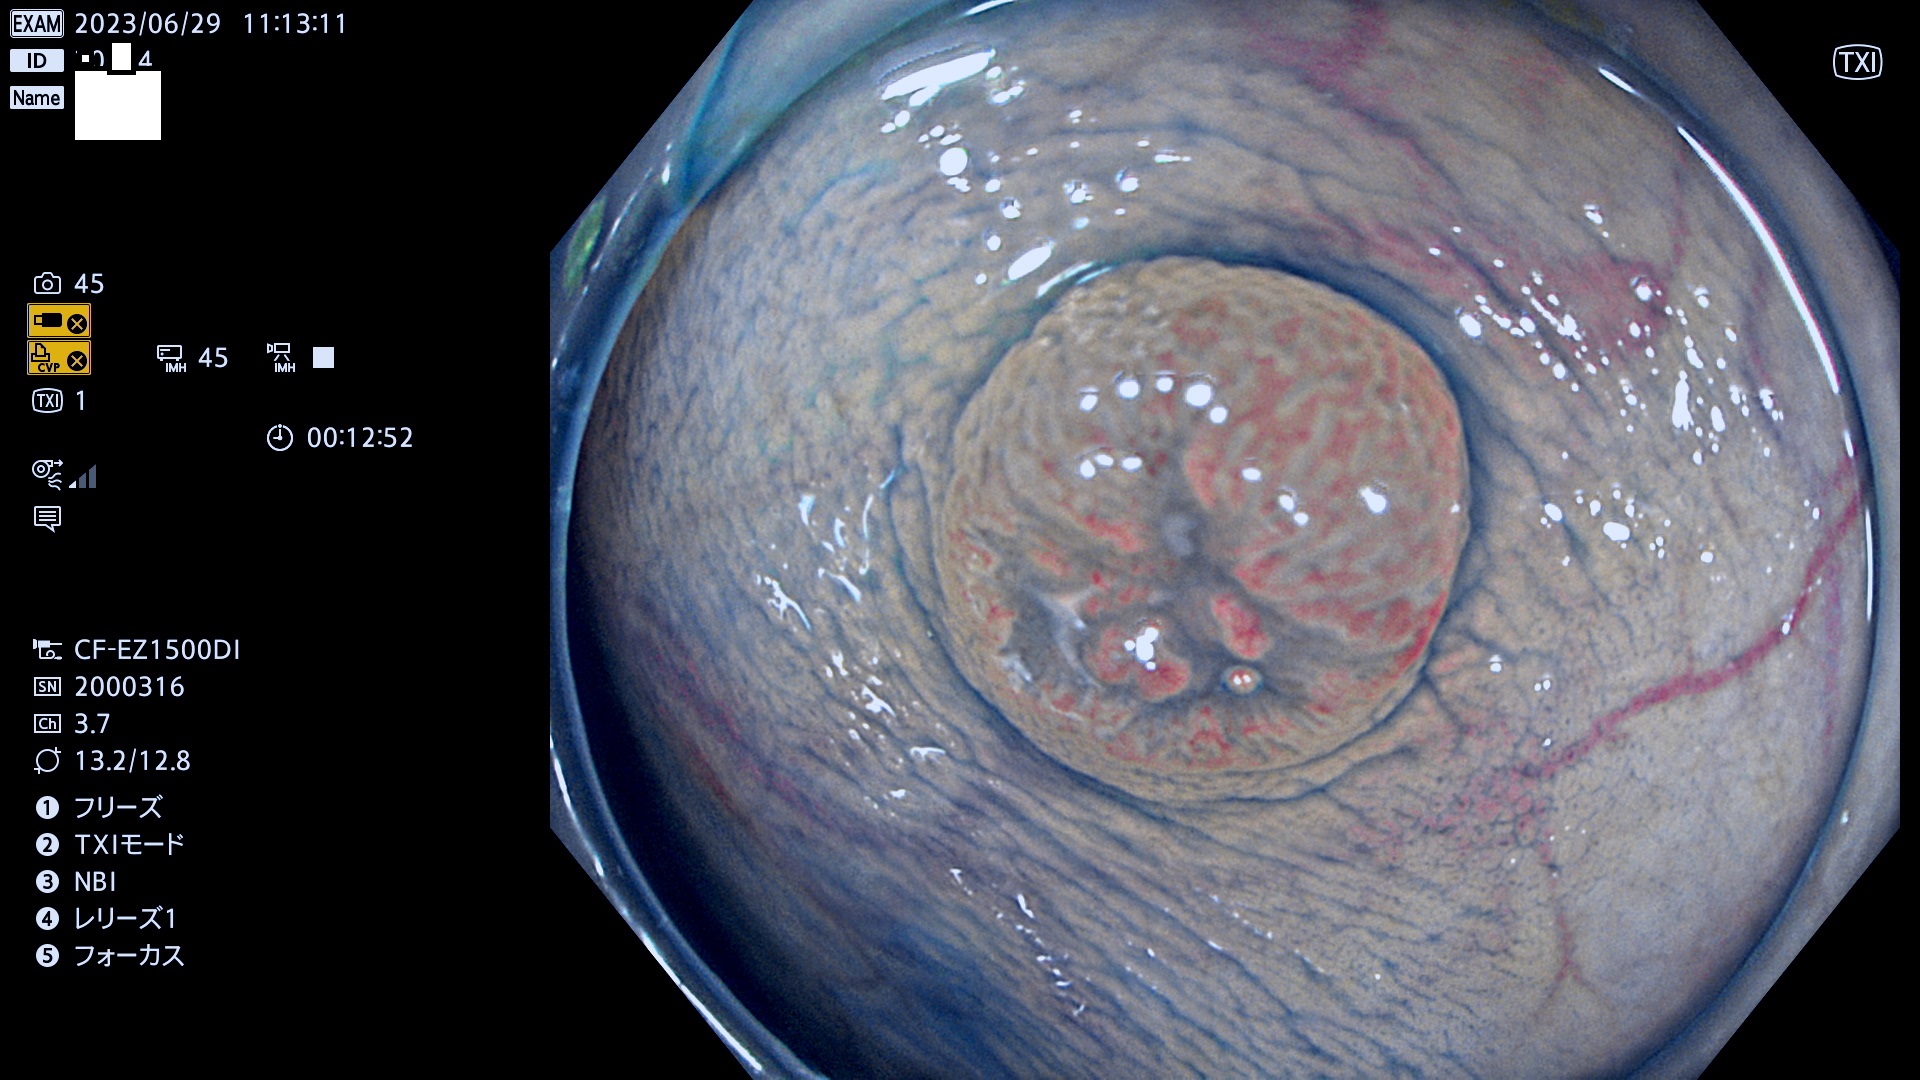

「表面型腫瘍」の中で、完全に平坦な物をUb、陥凹している物をUcと呼びます。平坦隆起型(Ua)よりも、発見が難しく危険な病変です。このタイプの発見率は「腺腫発見率」よりも、遥かに重要な意義があります。

抽出の対象期間 2023年6月29日(木)〜7月2(日)の4日間(48件の検査)8件